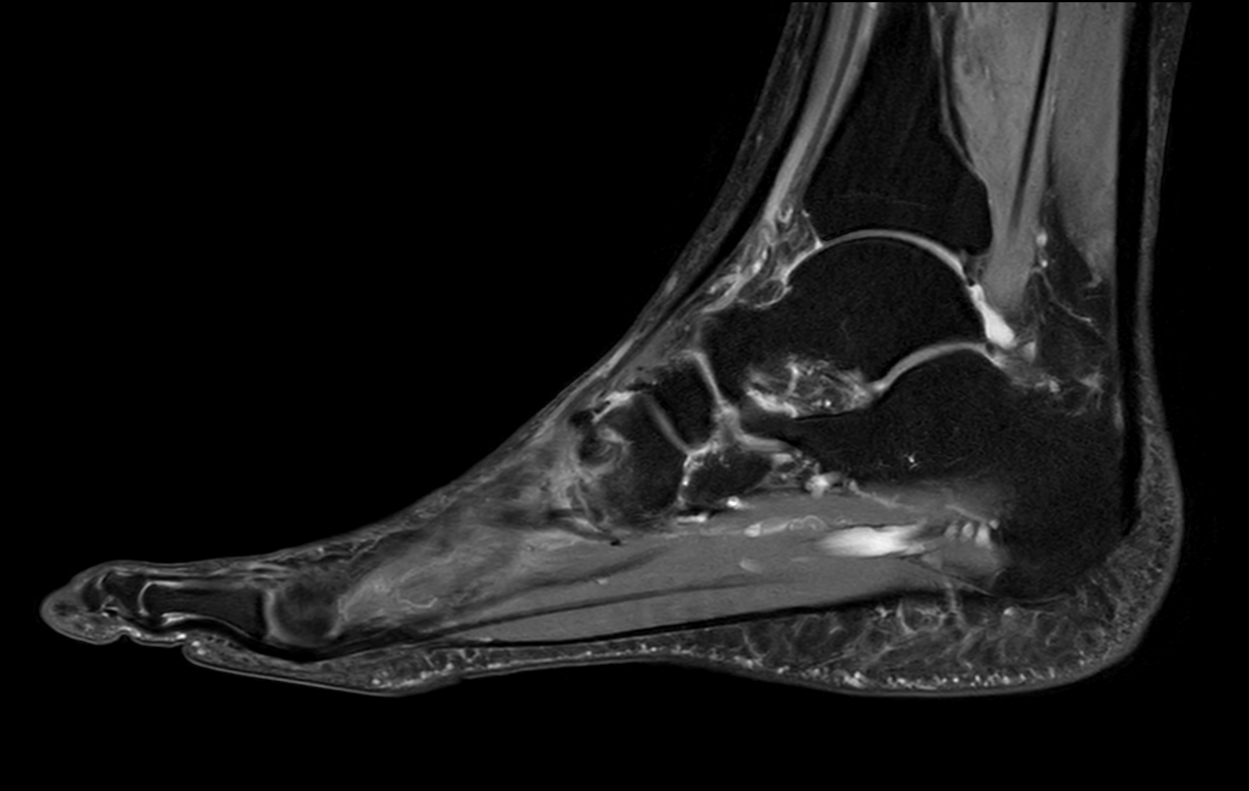

Ankle/Foot imaging post-amputation

Patient with partial amputation of the foot

Sagittal PDw mDIXON XD TSE (Water only)

Sagittal PDw mDIXON XD TSE (Partial FatSat)